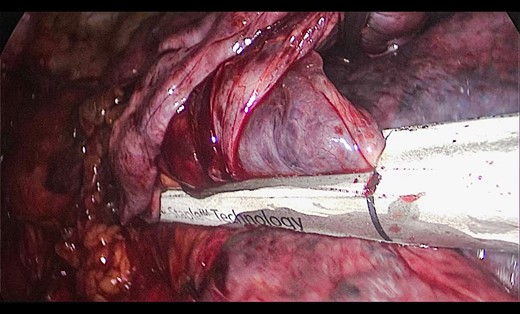

A 73-year-old male patient with a clinical history of COPD, lung emphysema and a 30-year smoking history was admitted to the ED due to a 24-h clinical picture of dyspnea immediately following a sudden bout of dry coughing. Physical examination showed a dyspneic patient, tachypnea of 25 rpm, heart rate of 85 bpm and blood Pressure of 135/75 mmHg along with central cyanosis. Chest exam showed a hyper-resonant right hemithorax along with reduced breath sounds. Initial chest X-ray revealed a large right-sided pneumothorax (Fig. 1). A right chest tube was placed in the ED. Emergency echocardiogram had no significant findings and spirometry showed suspected patterns of obstruction. Following patient stabilization, a high-resolution chest computed tomography (HRCT) was performed revealing extensive pan lobar emphysema throughout both lungs, para septal emphysema in both the anterior upper lobes and herniation of a left lung bullae through the anterior mediastinal pleura along with a right-sided pneumothorax with the chest tube in place with persistent air space (Fig. 2). The patient was taken to surgery where a right video-assisted thoracoscopic (VATS) approach showed severe lung emphysema and a contralateral herniated left lung bulla through the mediastinal pleura anterior to the pericardium (Fig. 3). Right pleurodesis was performed using Talc and a left posterior thoracoscopy showed a severe emphysematous left lung with a lingular herniated bulla to the right hemithorax through an anterior mediastinal pleural defect along with pleural adhesions (Figs 4 and 5). Thoracoscopic hernia reduction was performed along with bullectomy using 60 mm mechanical sutures (Fig. 6). Chest tubes were removed on POD 3 (right) and POD 4 (left). The patient had significant respiratory improvement and was discharged on POD 5.

Thoracoscopic view of transmediasinal herniation of pulmonary bulla to the right hemithorax (asterisk).